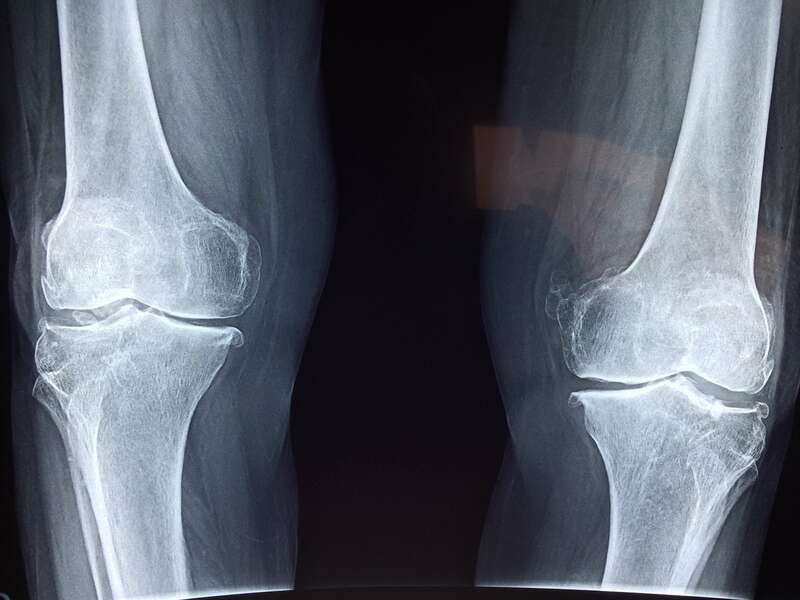

Elle sera confirmée par des examens radiologiques tels que des radiographies du genou. En cas de doute diagnostic ou afin de rechercher d’éventuelles lésions associées, un scanner et/ou une IRM pourront être prescrits.

L’arthrose n’entraine pas toujours des douleurs. On parle de dissociation radio-clinique : une arthrose visible radiologiquement n’est pas forcément responsable de douleurs. Dans ce cas, aucun traitement n’est nécessaire.